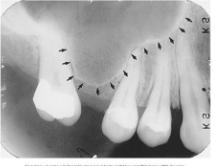

Maxillary Sinus

radiolucent area located above the apices of the premolar/molar areas in maxilla

(radiolucent)

Maxillary Tuberosity

radiopaque bulge distal to last tooth on max arch

(radiopaque)

Hamulus

radiopaque pointy projection located distal to max tuberosity

Zygomatic Arch

J or U shaped radiopaque area superior to the maxillary 1st molar region

What surrounds the maxillary sinus?

septa

What appears in the area of the maxillary canine and premolars?

inverted-y

(radiopaque, upside down y)